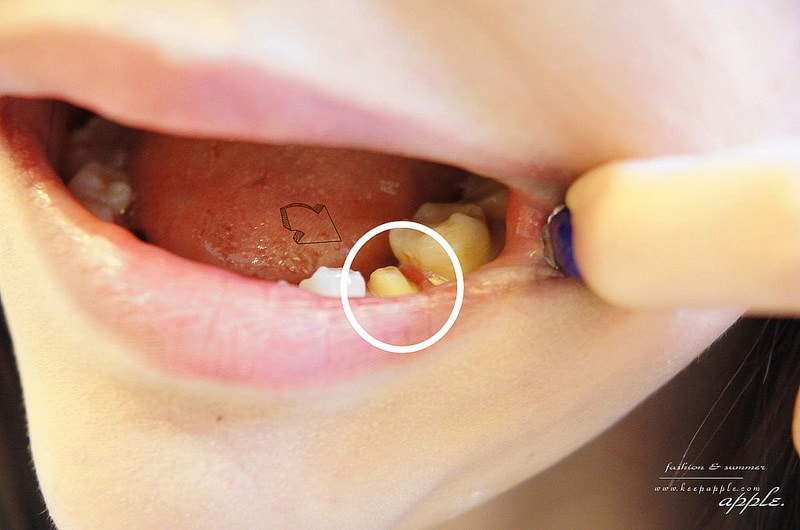

這顆就是要裝牙套的牙齒

會先像這樣磨成小小的

等一下好裝牙套

下次我就是要來做另外一顆牙的崁體

(有沒有注意到,黑黑的,看起來不好看><)

但如果沒有蛀到神經的話,醫師就會建議可以用崁體就好